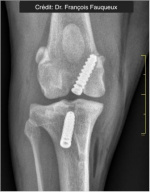

Radiologické snímky